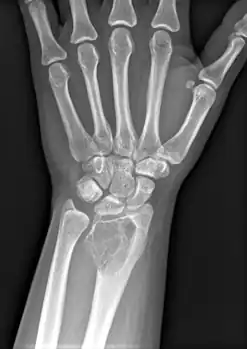

X-ray of a giant-cell bone tumor in the head of the fourth metacarpal of the left hand

Imaging

On X-ray, giant-cell tumors (GCTs) are lytic/lucent lesions that have an epiphyseal location and grow to the articular surface of the involved bone.[11] Radiologically the tumors may show characteristic 'soap bubble' appearance.[12] They are distinguishable from other bony tumors in that GCTs usually have a nonsclerotic and sharply defined border. About 5% of giant-cell tumors metastasize, usually to a lung, which may be benign metastasis,[13] when the diagnosis of giant-cell tumor is suspected, a chest X-ray or computed tomography may be needed. MRI can be used to assess intramedullary and soft tissue extension.